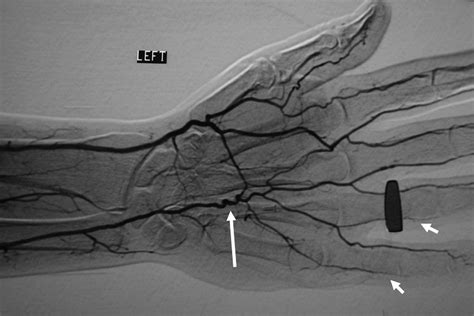

Correct diagnosis is paramount. Because the symptoms overlap with other vascular disorders, physicians usually employ a combination of clinical history and advanced imaging. A physical examination often includes the Allen’s test, which helps assess the patency of the ulnar and radial arteries. If HHS is suspected, the following diagnostic tools are typically utilized:

• Duplex Ultrasound: An excellent initial tool to visualize the blood flow and identify potential blockages or aneurysms.

• CT Angiography (CTA): Provides detailed imagery of the vascular anatomy and is highly effective at identifying aneurysms.

• Magnetic Resonance Angiography (MRA): A non-invasive method to evaluate the integrity of the arterial walls.

• Digital Subtraction Angiography (DSA): Considered the "gold standard" for definitive diagnosis, as it allows for real-time visualization of the blood flow within the hand.